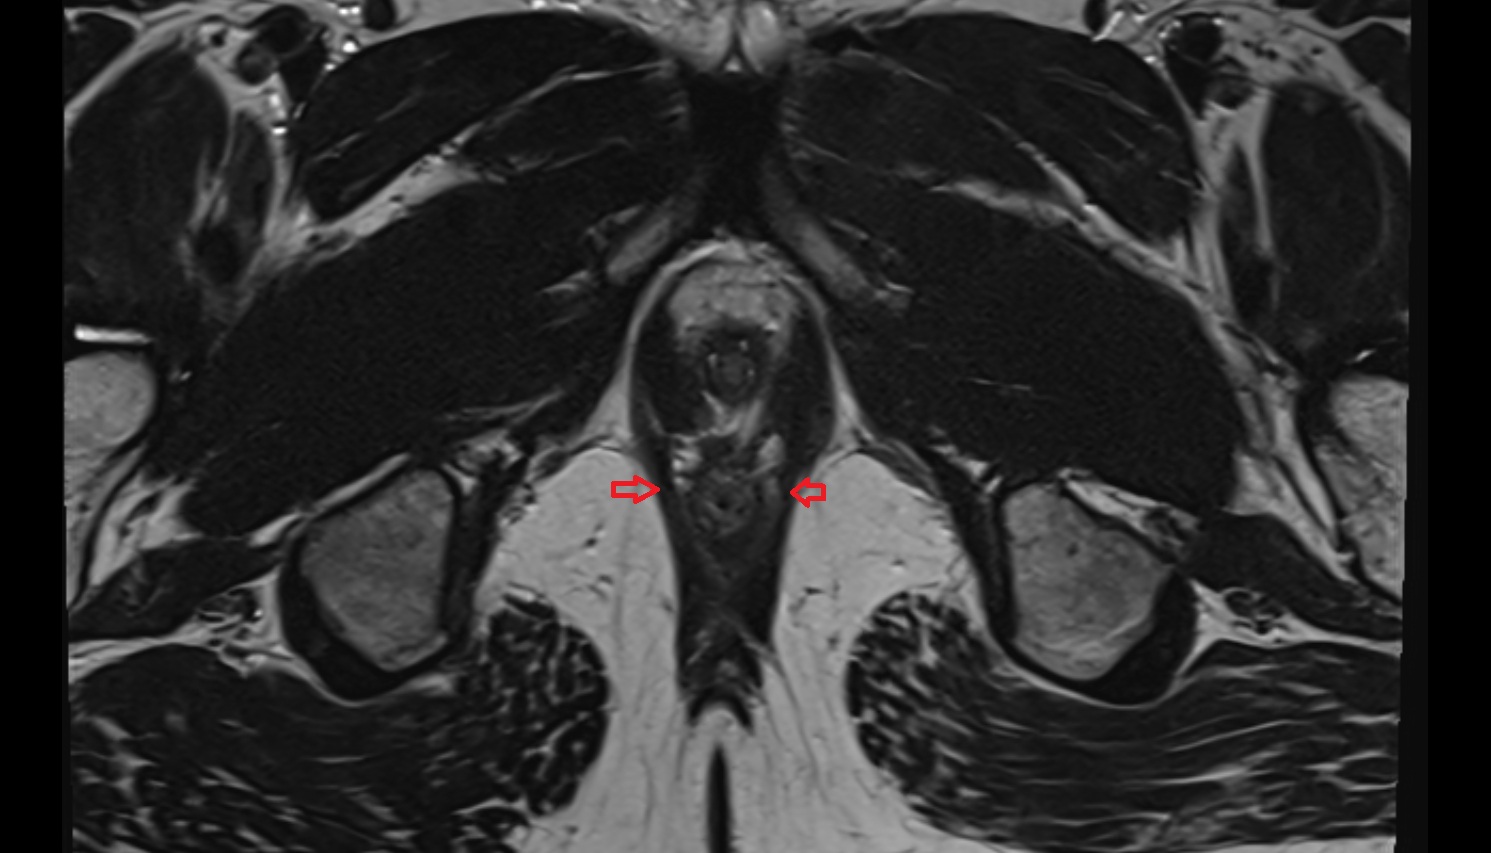

- Peripheral zone of prostate

- Anterior Fibromuscular Stroma of prostate

- Central zone of prostate

- Transitional zone of prostate

- Prostatic urethra